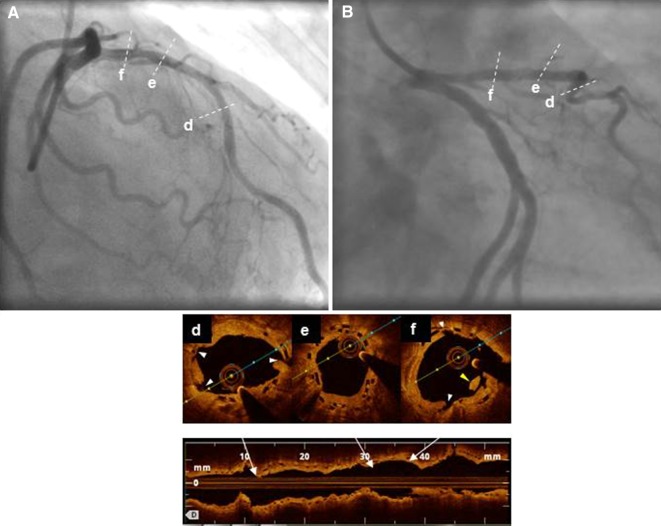

Fig. 3.

Final result after scoring balloon/drug-eluting balloon treatment. In A, B, the final angiographic appearance after balloon-only treatment of the restenosis. d–f Lumen expansion is clearly visible via optical coherence tomography (OCT). The white arrowheads show the lumen-surface marks achieved by the scoring elements. Intraluminal material caused by neointimal dissection is also observed (yellow arrowhead)